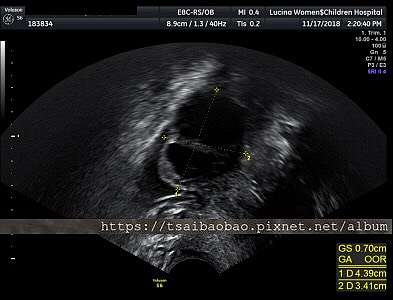

18 11 17 11 24 第二 三次回診 蔡胎芽登場 曼曼生活 Mannilife 痞客邦